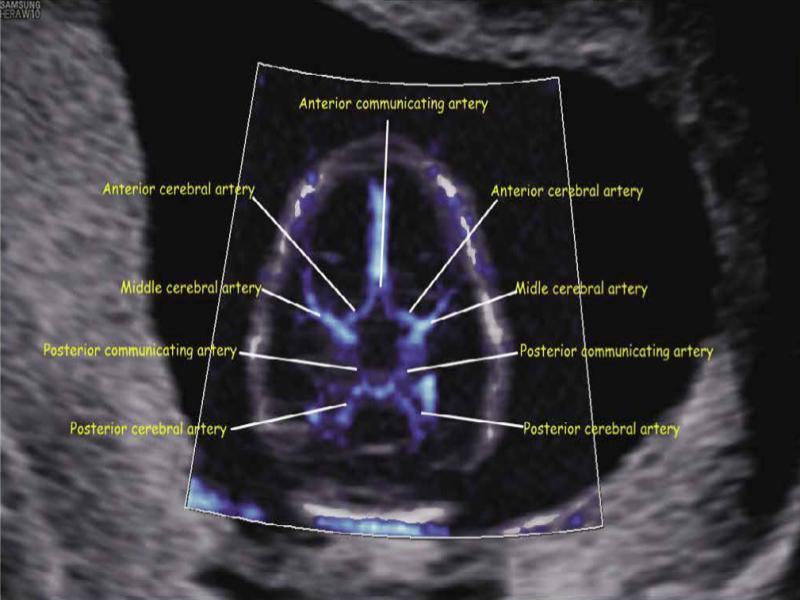

Fig. 2.

Axial view of the fetal brain at 12 + 4 weeks of gestation showing detailed vascular neuroanatomy of the circle of Willis using both MV-Flow and LumiFlow: anterior and posterior communicating arteries; anterior, middle, and posterior cerebral arteries